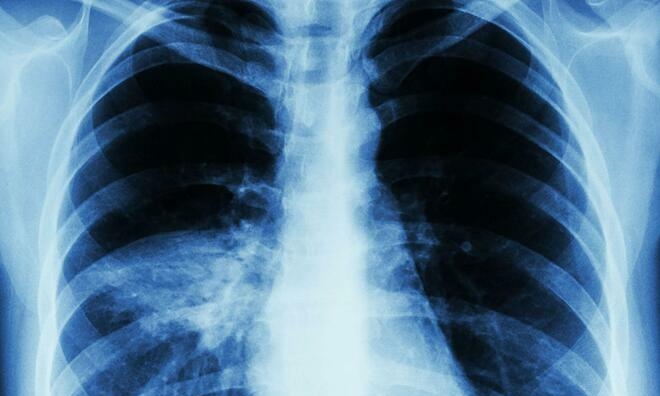

Viêm phổi là một căn bệnh nghiêm trọng có thể gây tử vong. Ảnh: News.Virginia